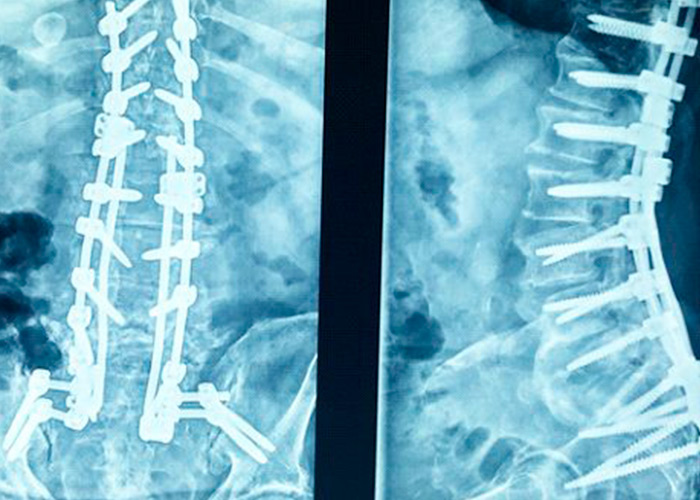

Operación

Diagnosticado de pseudoartrosis, realizamos recambio de tornillos con aumento de grosor y fijación con doble barra con tornillos ilíacos. No es posible realizar artrodesis intersomática L5-S1 por hundimiento de espacio discal intervertebral.

Postoperatorio

Evoluciona muy satisfactoriamente con mejoría importante del dolor y deambulación progresiva con estabilización en la marcha y sin requerir ayuda con bastón ni andador.